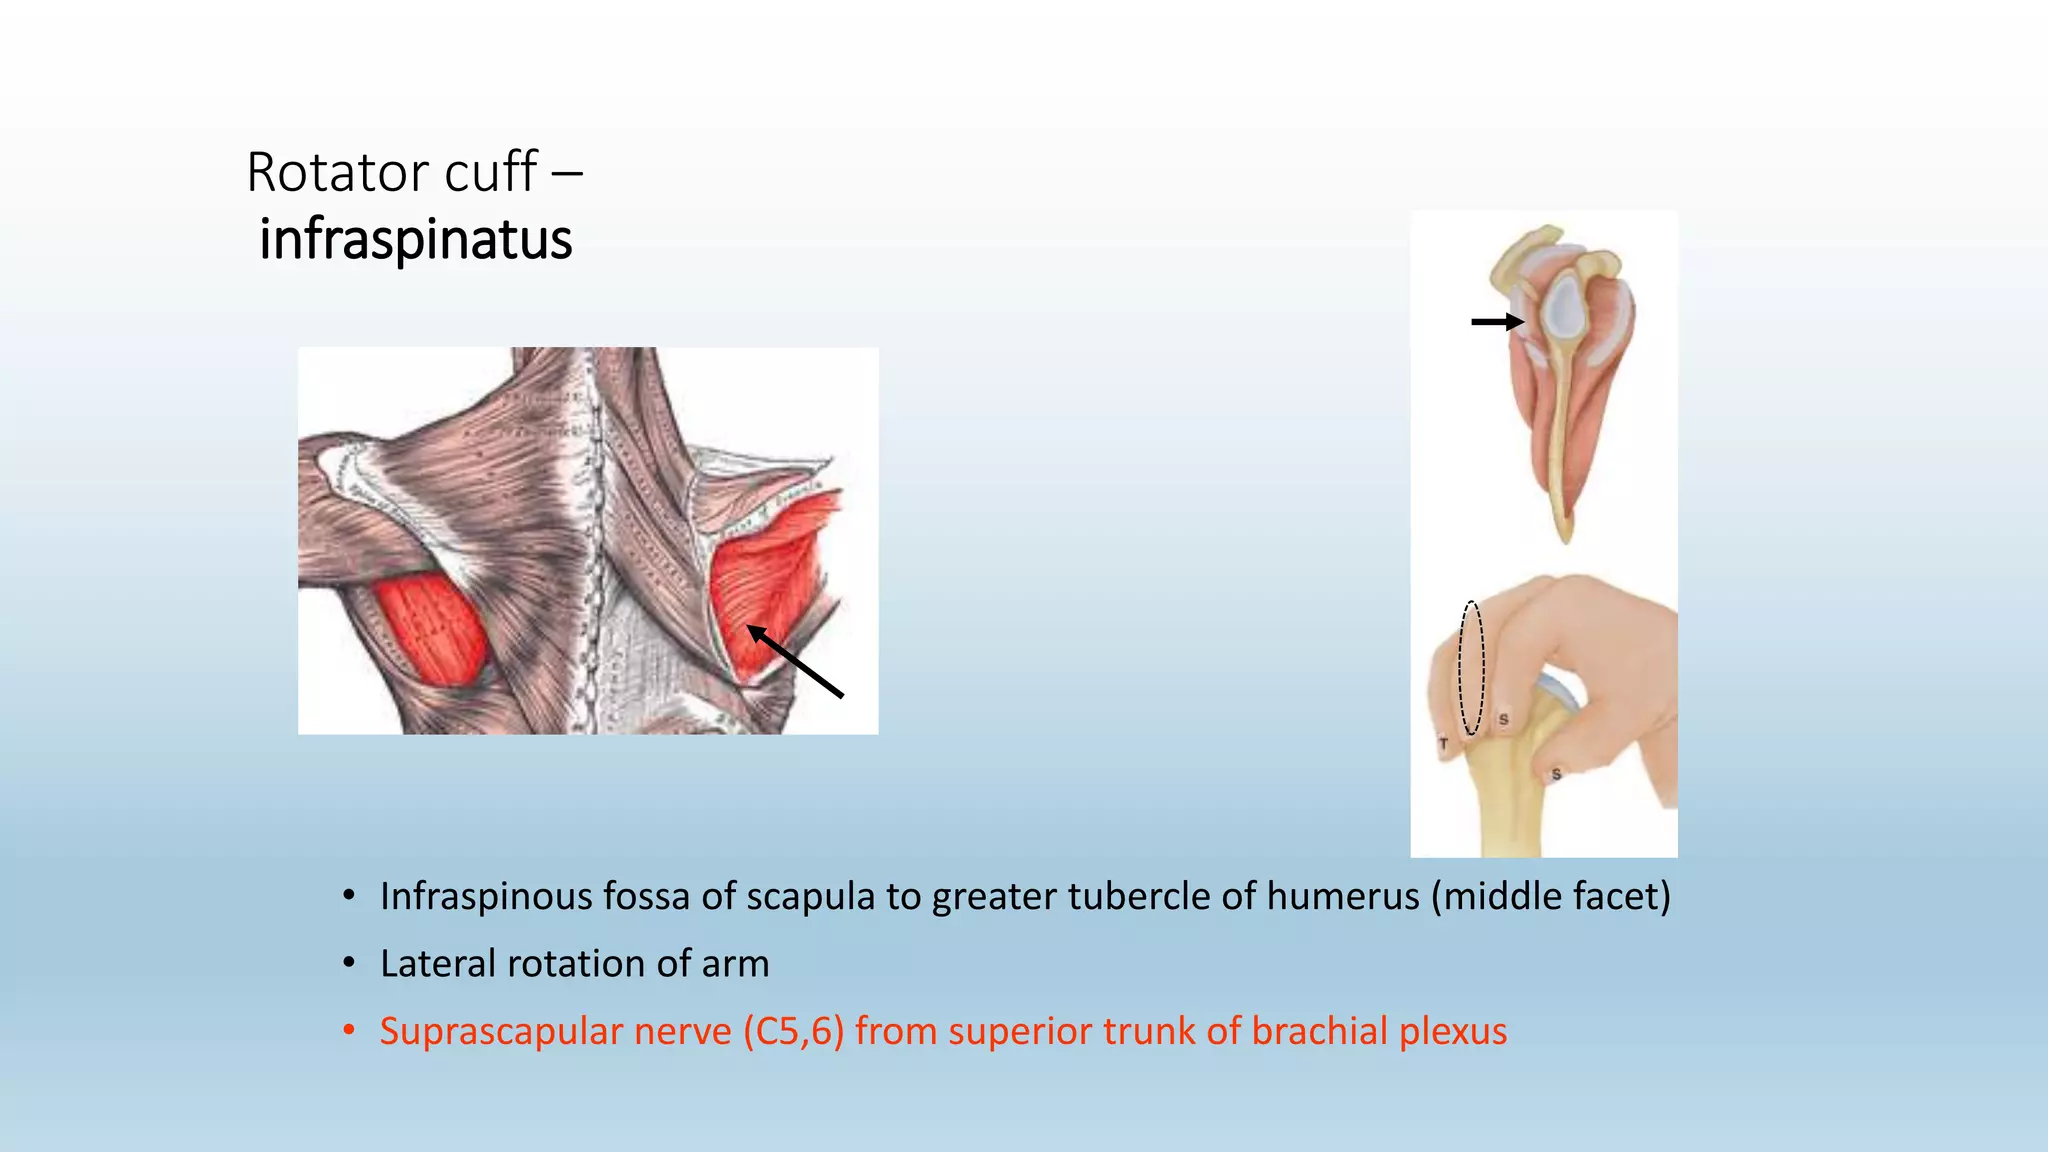

The document summarizes an anatomy revision session on the upper limb. It discusses various muscles of the upper limb including their origins, insertions, innervations and functions. Key muscles covered include the pectoralis major and minor, serratus anterior, deltoid, biceps brachii, brachialis, coracobrachialis, and triceps. It also discusses the rotator cuff muscles and muscles of the forearm including flexor carpi ulnaris and radialis. The session aims to help students identify upper limb muscles and understand their relations to nerves.